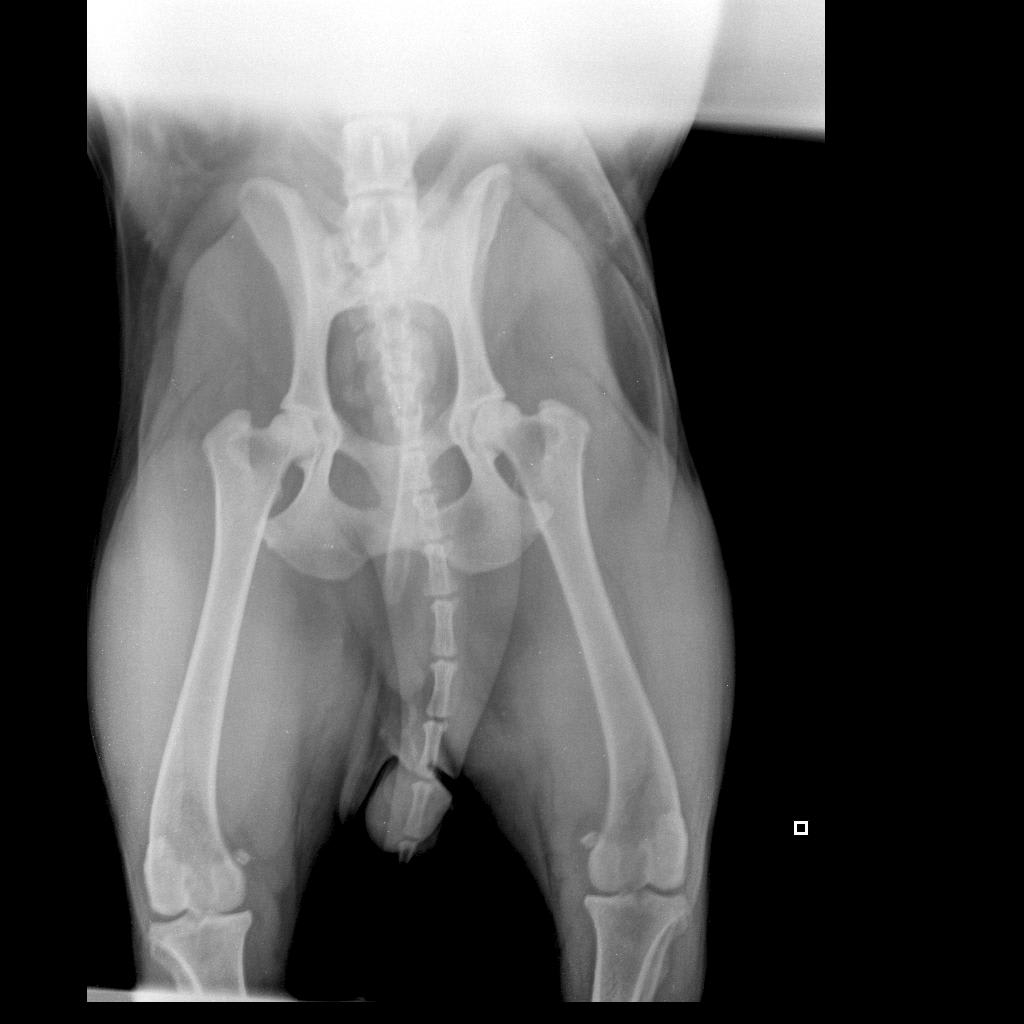

Pet's info: Dog | Labrador Retriever | Male | unneutered | 3 years and 10 months old | 75 lbs

Hi, My 4 year old black lab had a bike accident. The mylogram shows overriding fracture at T13-L1 of his spine. Even though his very has suggested euthanasia, I want to give him a chance. Could you please tell me if keeping him alive would lead to medical complications or would have serious effects on his health? I am willing to put in all the hardworkd required to keep him happy, unless euthanasia is the only way.

Hi and thank you for your post. While surgery may be possible, this should be done at a specialty or veterinary teaching hospital at a University for sure. It is highly likely Jordan will have multiple neurological deficits after surgery and make never be able to use his legs normally. He may have problems defecating and urinating. The road for recovery will be long and arduous for both you and Jordan. He will need lots of physical rehabilitative therapy and constant round the clock care for quite some time. How long will depend on his response to treatment, therapy and medication. Best to you and Jordan! Thank you for using Petco Pet Education Center, formerly Petcoach!